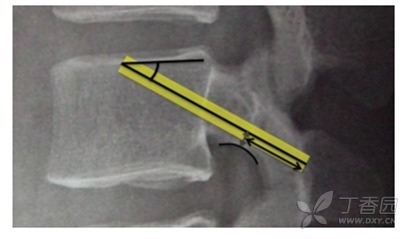

图 2 最佳的 CBT 螺钉轨迹的矢状面示意图:进钉点为峡部偏下位置、头倾 25° 到 30 °,经椎弓根的下部,如此螺钉在椎板及椎体内长度最长并止于椎体终板中心位置

以上结果表明:CBT 螺钉固定稳定性受到操作技术(如头倾角度及椎板内螺钉长度)及患者本身(骨密度) 等因素的影响,最佳的置钉轨迹是头倾 25° 到 30 °,沿椎弓根下方边界置入,这样可保证螺钉与椎板有最大的接触面积及在椎体内有最佳的长度。